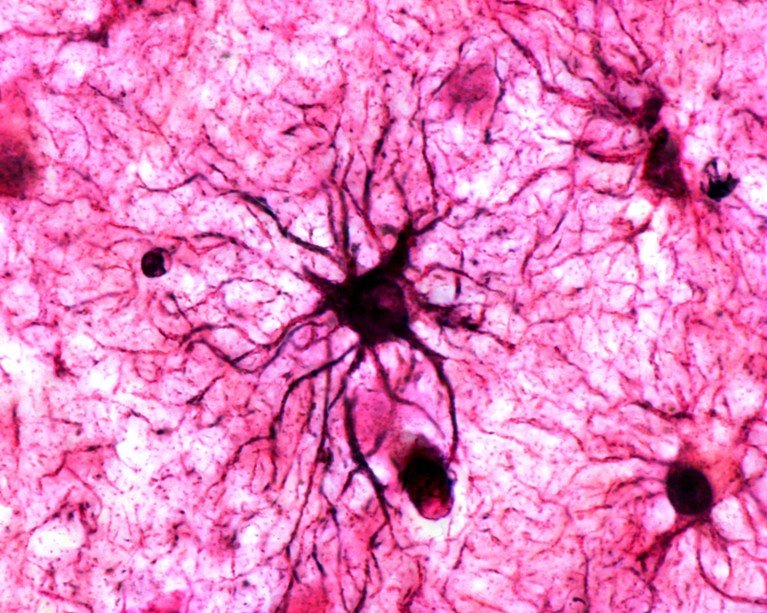

A type of brain cell called astrocytes play a crucial role in stabilizing memories in the brain.Credit: Jose Calvo/SPL

يلعب نوع من خلايا الدماغ يسمى الخلايا النجمية دورًا حاسمًا في تثبيت الذكريات في الدماغ.الائتمان: خوسيه كالفو / SPL

الخلايا النجمية – خلايا الدماغ التي كان يُعتقد في السابق أنها تدعم الخلايا العصبية – لديها بالفعل دور رئيسي في تثبيت الذكريات للاستدعاء على المدى الطويل. وقد وجد الباحثون ذلك في الفئران فوس، وهو الجين المرتبط بنشاط الخلية، تم التعبير عنه بشكل كبير في الخلايا النجمية للفئران التي عادت إلى الأقفاص التي تم تكييفها لربطها بالخوف. ووجد الفريق أيضًا أن الخلايا النجمية شديدة النشاط تنتج المزيد من المستقبلات التي تستجيب للناقل العصبي النورادرينالين، مما يسمح لها بالتواصل مع الخلايا العصبية. وتشير النتائج إلى أن الخلايا النجمية، إلى جانب الخلايا العصبية، تشارك بنشاط في خلق آثار مادية للذكريات في الدماغ.